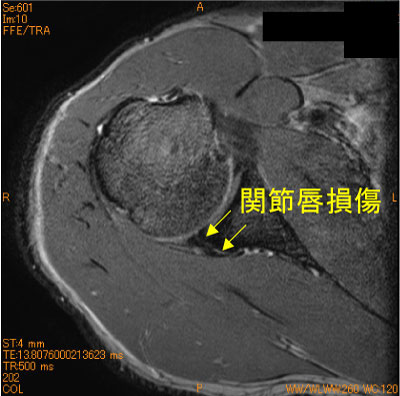

投球障害肩の後下方関節唇損傷-肩関節MRI-

30代男性。投球時の疼痛。野球歴30年。

後下方関節窩が丸みをおびるslant appearanceあり。同部の関節唇損傷を伴っている。

この関節唇損傷はKim’ lesionとよばれる。

投球障害肩で、このような疾患があることを知らないと見落とす可能性が高い。